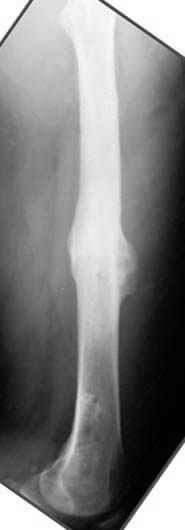

Несколько снимков из моей коллекции, чтобы разьяснить, почему мы до сих пор делаем различные варианты остеотомии.

N3 рисунок окончательный снимок, после операции моя рентгенограмма должен выглядеть примерно как эта картина. На N4 снимке клин перед удалением; N5 послеоперации 3 нед.; N6 окончательная рентгенограмма.

пластическая модель; и коррекция бедра аппаратом Илизарова.

Почему не замена гвоздя с рассверливанием, а аппарат?

Отправитель: Alexander Chelnokov 23 Ноябрь 2004, 21:29

хотя даже если бы и инфекция , то nail exchange с рассверливанием канала - вариант дебрайдмента) Я думаю, что последовательность развития событий:

Узкий к-м канал - тонкий гвоздь- усталостный перелом дистальных винтов - развитие нестабильности и как ее результат остеолиз вокруг гвоздя - деформация анатомической оси бедра. Похоже, что я понял почему аппарат, а не новый гвоздь:-)